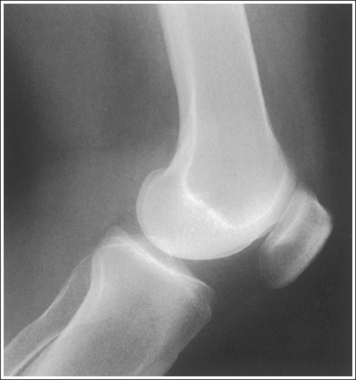

See Figures 6-80 and 6-81 and Box 6-17.

The patella is situated proximal to the patellar surface of the femur, and the patellofemoral joint is open.

The distal articulating surfaces of the medial and lateral femoral condyles are superimposed, and the knee joint space is open.

The anterior and posterior surfaces of the medial and lateral femoral condyles are superimposed, and the tibia is partially superimposed over the fibular head.

The knee joint is at the center of the exposure field. One fourth of the distal femur and proximal lower leg and the surrounding knee soft tissue are included within the collimated field.

• Center the central ray to the midline of the knee at the level of the knee joint space, which is located 1 inch (2.5 cm) distal to the palpable medial epicondyle, to center the knee joint in the collimated field. Open the longitudinal collimation enough to include one fourth of the distal femur and proximal lower leg. Transverse collimation should be to within 0.5 inch (1.25 cm) of the knee skin line.